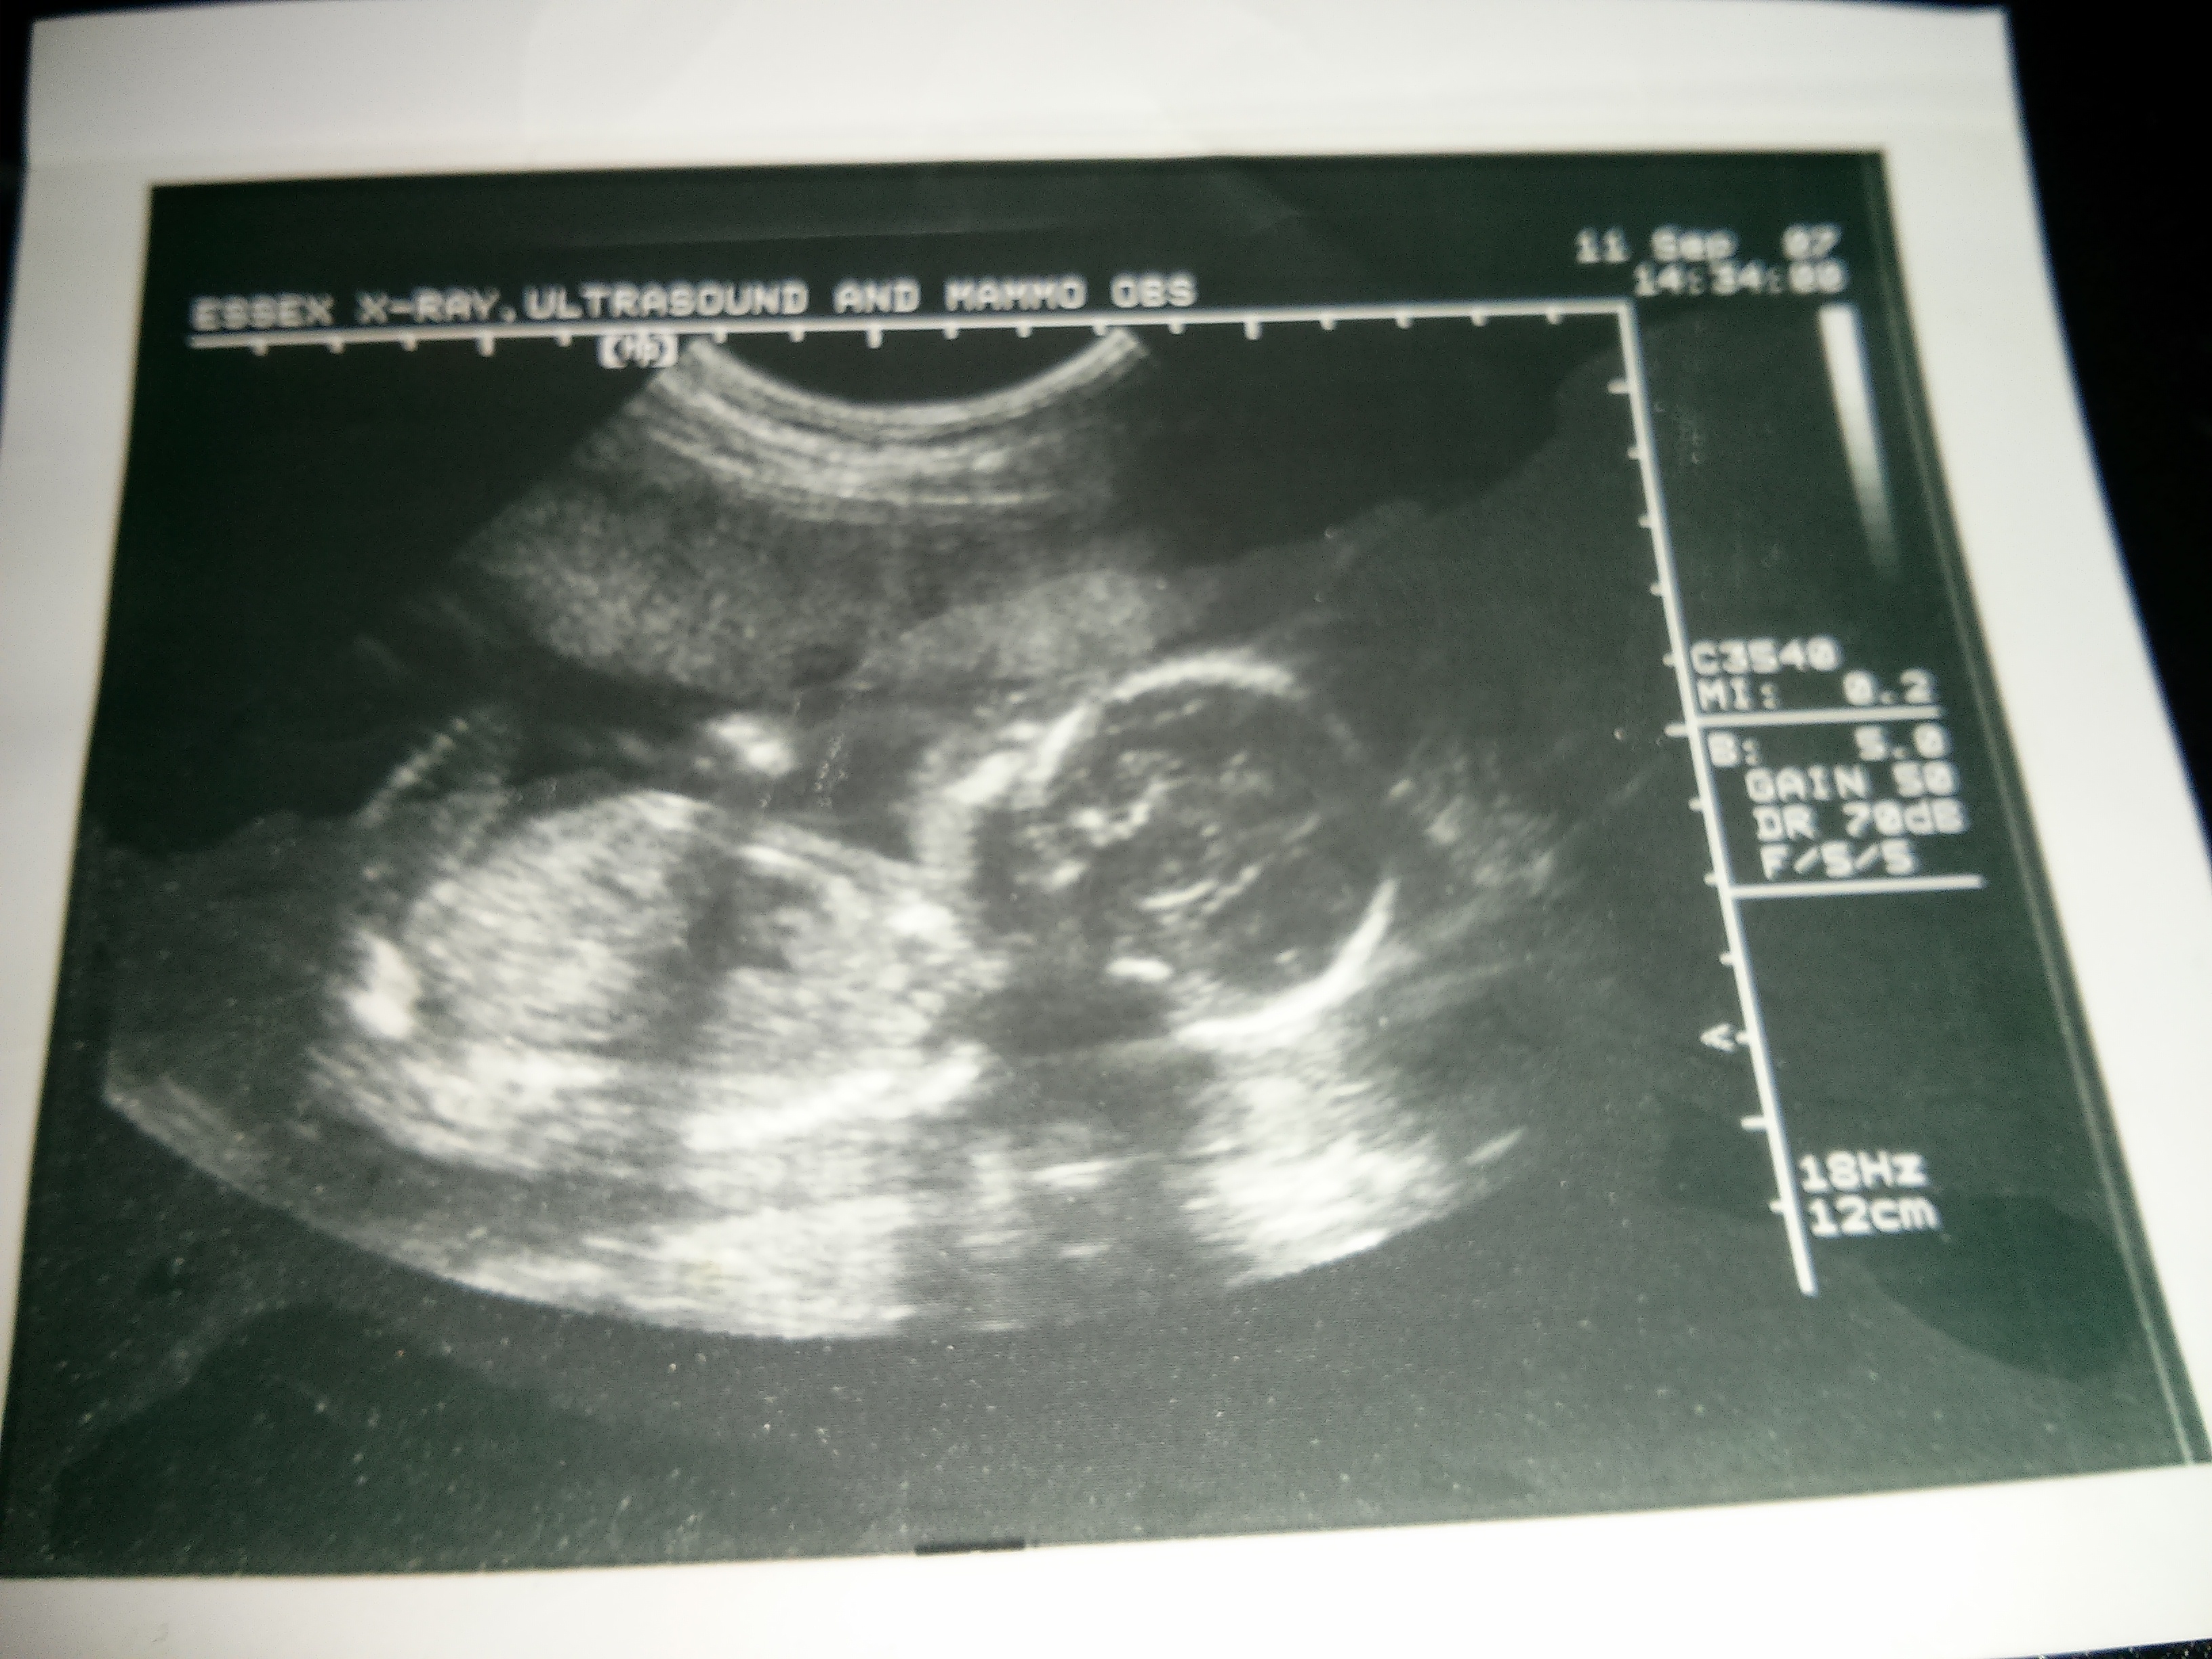

Hello I was wondering if anyone can take a guess on my first child's scan I'm currently in my two week wait TTC #2 and thought this would be fun and help pass the time Attachment 12847Attachment 12847

Girl? Take a look at mine if you want something to do lol x